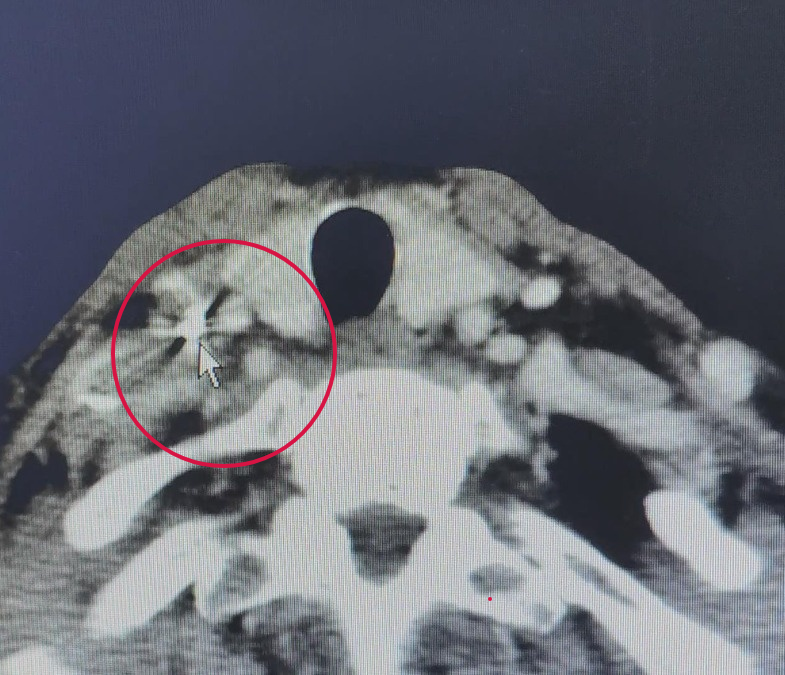

2023年11月

光動力治療前

影像結(jié)果

2024年6月

兩次光動力治療后7個月復查結(jié)果

經(jīng)過2次光動力治療、1次碘粒子植入后,老張鎖骨上的淋巴結(jié)較前縮小,食管上已經(jīng)無糜爛的情況,基本看不見腫瘤的存在。對于老張來說,不用“挨一刀”,病情有好轉(zhuǎn),生活質(zhì)量沒影響,自己又能吃能睡,他和家屬都很滿意。后續(xù)老張將繼續(xù)口服化療藥維持治療。